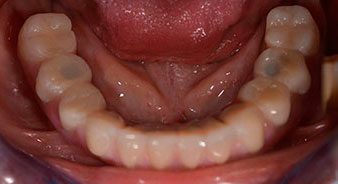

La paciente de 64 años se presentó con una dentición residual compuesta por las piezas dentales 38, 33 y 43 en el maxilar inferior y con una prótesis temporal fijada con ganchos en el maxilar inferior (figs. 1 y 2).